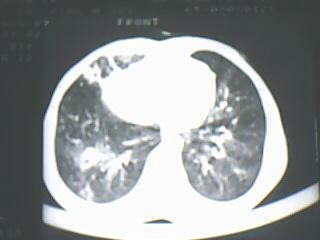

以下是引用随光逐影在2009-8-7 15:40:00的发言:[br]考虑右肺继发性肺结核并右肺上叶空洞形成,两肺支气管播散;不排除右肺上叶空洞内霉菌感染可能。

以下是引用jiangjing在2009-8-7 14:38:00的发言:[br]右上肺张力空洞,酐珞坏死灶,支气管扩张,多发播散灶,纵膈淋巴结显示,胸膜增厚---结核